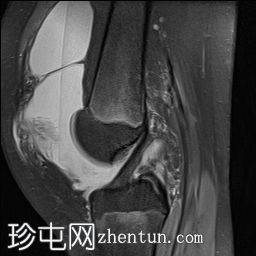

矢状位

T1加权像

PD脂肪抑制序列

梯度回波序列

关节内大量积血,可见血细胞比容增高征。股骨外侧髁前部及髌骨内侧可见挫伤性微骨折。髌骨内侧支持带及髌股内侧韧带水肿增厚。髌骨内侧关节面下关节软骨浸润,提示I期骨软骨损伤。

髌骨外侧隐窝可见游离体,其信号强度与关节软骨一致,提示髌骨关节软骨外剥离损伤。股骨滑车和股骨关节软骨正常。

胫骨近端和腓骨骨骺以及股骨远端延伸至干骺端的骨骺周围可见局灶性骨髓水肿。这些提示存在局灶性骨骺周围水肿区。

十字韧带和侧副韧带正常。半月板正常。股四头肌腱和髌腱正常。

该病例具有短暂性髌骨外侧脱位复位损伤的特征性表现,包括预期的骨挫伤模式、内侧髌骨支持带/内侧髌股韧带损伤、髌骨骨软骨损伤以及髌骨软骨游离体。